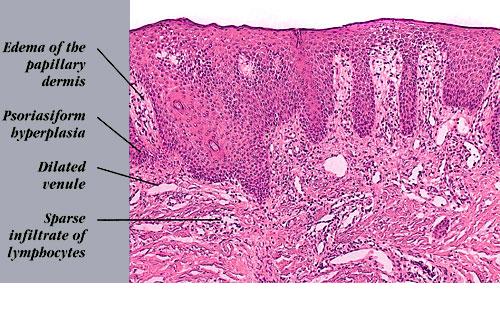

Erythroderma of psoriasis = أحمرية الجلد الصدفية